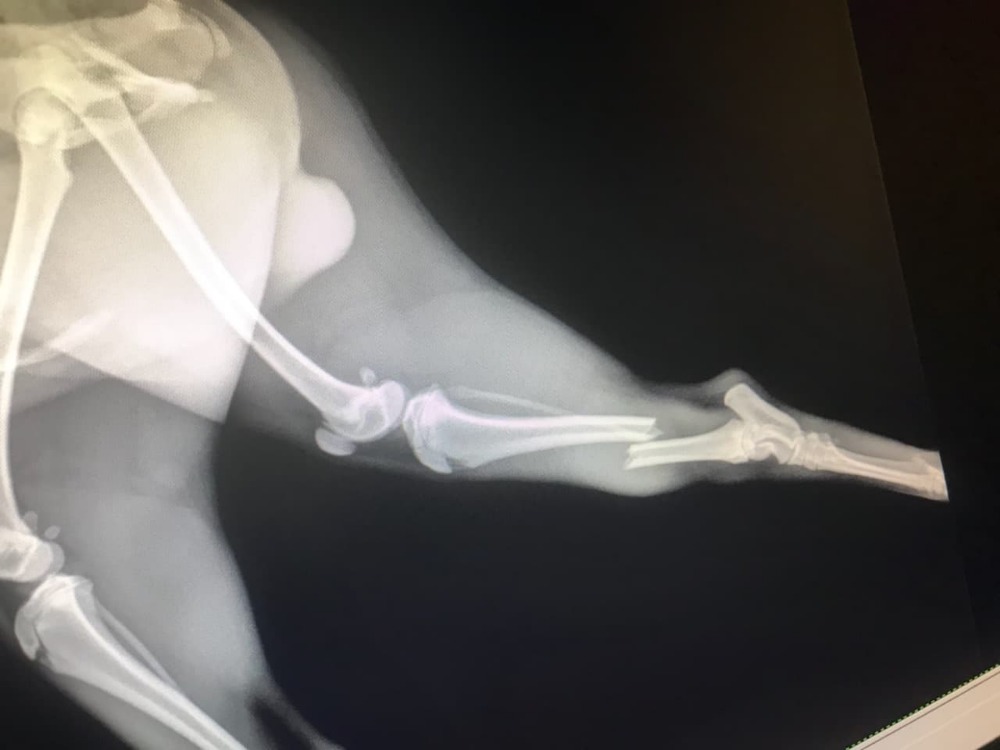

05/03/18- When I was at work, Maple got out of the house and ran out into the street (Bolsa and Bushard) and was hit by an oncoming vehicle. Fortunately Maple survived but was left with a broken leg and damaged spine. The vet said that it would cost 3k for the leg surgery and 7k for the spine surgery and I don't have the money to pay for his medical expenses. I know that people are always fundraising for other causes but if you can even spare a dollar, I would really appreciate it. He's the reason I wake up everyday with a smile. He's the happiest dog in the world and seeing him so sad breaks my heart =((